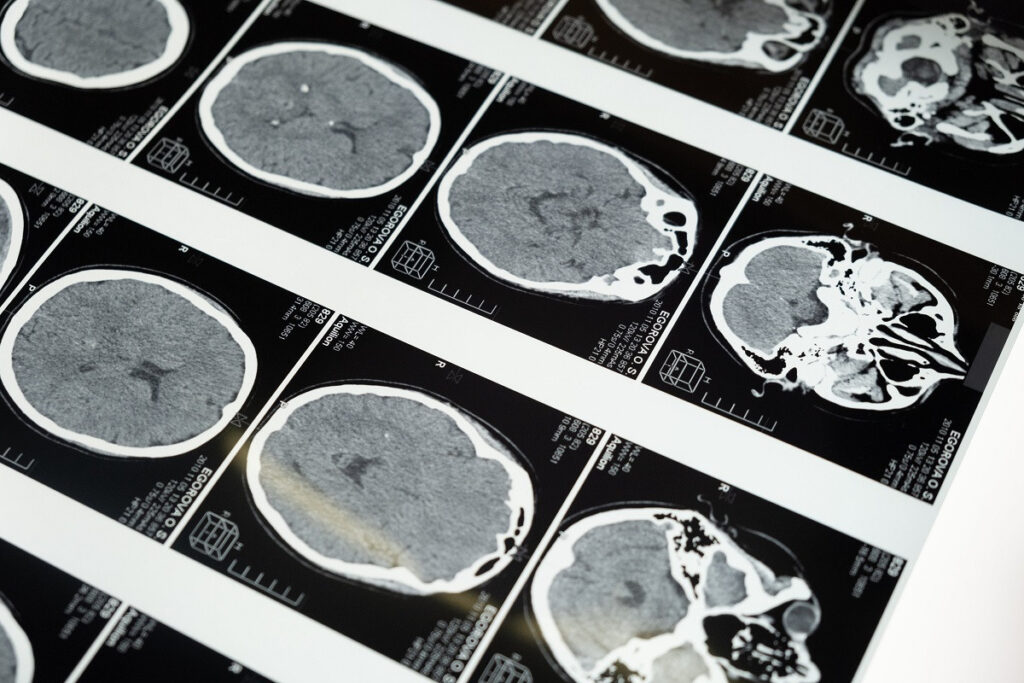

Όπως αναλύει σε εκτενές του άρθρο – ανάλυση το MIT, στη μελέτη της Δυτικής Βιρτζίνια, τρία άτομα με ήπια νόσο Αλτσχάιμερ έλαβαν μηνιαίες δόσεις aducanumab, ένα εργαστηριακό αντίσωμα που χορηγείται μέσω IV. Αυτό το φάρμακο, που εγκρίθηκε για πρώτη φορά το 2021, βοηθά στην απομάκρυνση του βήτα-αμυλοειδούς, ενός θραύσματος πρωτεΐνης που συσσωρεύεται στους εγκεφάλους των ατόμων με νόσο του Αλτσχάιμερ. (Σημειώστε ότι η έγκριση του φαρμάκου ήταν αμφιλεγόμενη και δεν είναι ακόμα σαφές εάν επιβραδύνει την εξέλιξη της νόσου). Μετά την έγχυση, οι ερευνητές αντιμετώπισαν συγκεκριμένες περιοχές του εγκεφάλου των ασθενών με εστιασμένο υπέρηχο, αλλά μόνο στη μία πλευρά. Αυτό τους επέτρεψε να χρησιμοποιήσουν το άλλο μισό του εγκεφάλου ως έλεγχο. Οι σαρώσεις PET αποκάλυψαν μεγαλύτερη μείωση στις πλάκες αμυλοειδούς στις περιοχές που υποβλήθηκαν σε θεραπεία με υπερήχους από ό,τι στις ίδιες περιοχές στην πλευρά του εγκεφάλου που δεν υποβλήθηκε σε θεραπεία, υποδηλώνοντας ότι μεγαλύτερο μέρος του αντισώματος εισχωρούσε στον εγκέφαλο στην υπό θεραπεία πλευρά.

Το aducanumab «καθάρισε» τις πλάκες χωρίς υπερηχογράφημα, αλλά χρειάζεται πολύς χρόνος, ίσως εν μέρει επειδή το αντίσωμα δυσκολεύεται να εισέλθει στον εγκέφαλο, σημειώνουν οι επιστήμονες. «Αντί να χρησιμοποιούμε τη θεραπεία ενδοφλέβια για 18 έως 24 μήνες για να δούμε τη μείωση της πλάκας, θέλουμε να δούμε αν μπορούμε να επιτύχουμε αυτή τη μείωση σε λίγους μήνες», λέει ο Ali Rezai, νευροχειρουργός στο Πανεπιστήμιο Rockefeller Neuroscience Institute της Δυτικής Βιρτζίνια και συγγραφέας της νέας μελέτης. Η μείωση του χρόνου που απαιτείται για να καθαριστούν αυτές οι πλάκες μπορεί να βοηθήσει στην επιβράδυνση της απώλειας μνήμης και των γνωστικών προβλημάτων που καθορίζουν την ασθένεια.

Η συσκευή που χρησιμοποιείται για τη στόχευση και την παράδοση των κυμάτων υπερήχων, που αναπτύχθηκε από μια εταιρεία που ονομάζεται Insightec, αποτελείται από μια μηχανή μαγνητικής τομογραφίας και ένα κράνος με μορφοτροπείς υπερήχων. Είναι εγκεκριμένο από τον FDA, αλλά για έναν εντελώς διαφορετικό σκοπό: να βοηθήσει να σταματήσει ο τρόμος σε άτομα με Πάρκινσον δημιουργώντας βλάβες στον εγκέφαλο. «Για να ανοίξουμε τον αιματοεγκεφαλικό φραγμό, κάνουμε ενδοφλέβια ένεση στα άτομα με μικροφυσαλίδες», λέει ο Rezai. Αυτές οι μικροσκοπικές φυσαλίδες αερίου, που χρησιμοποιούνται συνήθως ως παράγοντας αντίθεσης, ταξιδεύουν μέσω της κυκλοφορίας του αίματος. Χρησιμοποιώντας τη μαγνητική τομογραφία, οι ερευνητές μπορούν να στοχεύσουν τα κύματα υπερήχων σε πολύ συγκεκριμένα μέρη του εγκεφάλου «με ακρίβεια χιλιοστού», προσθέτει ο Rezai. Όταν τα κύματα χτυπούν τις μικροφυσαλίδες, οι φυσαλίδες αρχίζουν να διαστέλλονται και να συστέλλονται, σπρώχνοντας φυσικά τα σφιχτά συσκευασμένα κύτταρα που επενδύουν τα τριχοειδή αγγεία του εγκεφάλου. «Αυτό το προσωρινό άνοιγμα μπορεί να διαρκέσει έως και 48 ώρες, πράγμα που σημαίνει ότι κατά τη διάρκεια αυτών των 48 ωρών, μπορείτε να έχετε αυξημένη διείσδυση στον εγκέφαλο των θεραπειών και των φαρμάκων», πρόσθεσε.